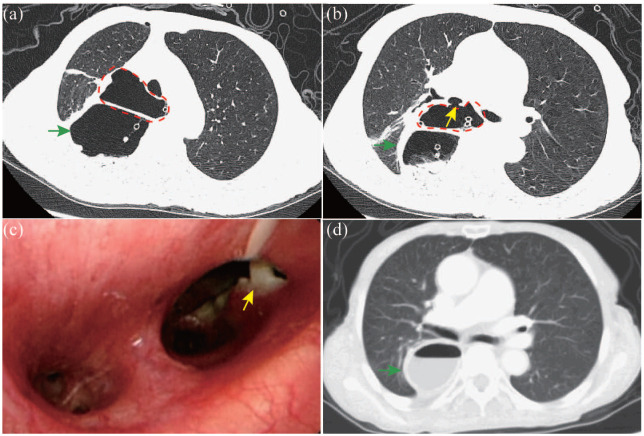

近年来,食管切除术后常见的术后并发症越来越受到重视。然而,对罕见并发症的关注还不够,这些并发症如果不及时诊断往往会导致严重后果。在这篇文章中,我们将介绍食管切除术后罕见并发症的临床和影像学特征,以及预防和处理这些并发症的策略。这些罕见的并发症分为四组:食管代用品相关并发症、胸导管相关并发症、疝气相关并发症和经壁Hem-o-lok夹移位。食管代用品相关并发症包括多余的导管和导管坏死。我们进一步将冗余管道分类为长度冗余管道,宽度冗余管道或两种冗余的组合。胸导管相关并发症包括难治性乳糜胸和乳糜纵隔。难治性乳糜胸是一种建立良好的医学、介入甚至外科治疗策略都难以治疗的乳糜胸,而乳糜纵隔是一种罕见的疾病,其特征是乳糜在纵隔积聚。疝相关并发症可分为裂孔疝、心后肺疝、肋间肺疝、套管针部位疝、胸骨后间隙或心包内疝和肠系膜缺损。经壁Hem-o-lok夹移动包括穿透气管、导管或两者。胸外科医生应熟悉食管切除术的罕见并发症,这些并发症大多是严重的,需要早期准确诊断并妥善处理。对罕见并发症的干预选择取决于患者的一般情况、并发症的具体类型、并发症的严重程度、重建途径、可用的医疗资源和外科医生的偏好等因素。为了将这些并发症的风险降到最低,食管切除术和预防方法需要标准化。

In recent years, common postoperative complications after esophagectomy have received increasing attention. However, the attention paid to rare complications, which often lead to serious consequences if they are not diagnosed in a timely manner, has not been sufficient. In this article, we present both the clinical and imaging features of rare complications following esophagectomy and strategies for their prevention and management. These rare complications are classified into four groups: esophageal substitute-related complications, thoracic duct-related complications, hernia-related complications, and transmural Hem-o-lok clip migration. Esophageal substitute-related complications include redundant conduits and conduit necrosis. We further classify redundant conduits as length-redundant conduits, width-redundant conduits, or a combination of both redundancies. Thoracic duct-related complications include refractory chylothorax and chylomediastinum. Refractory chylothorax is chylothorax refractory to well-established medical, interventional, and even surgical strategies, whereas chylomediastinum is a rare condition characterized by the accumulation of chyle in the mediastinum. Hernia-related complications are subclassified as hiatal hernias, retrocardiac lung hernias, intercostal lung hernias, trocar-site hernias, hernias internal to the retrosternal space or pericardium, and mesenteric defects. Transmural Hem-o-lok clip migration includes penetration of the trachea, conduit, or both. Thoracic surgeons should familiarize themselves with the rare complications of esophagectomy, most of which are serious conditions that require early and accurate diagnosis for proper management. The choice of intervention for rare complications depends on factors such as the patient's general condition, the specific type of complication, the complication severity, the reconstruction route, the available medical resources, and the surgeon's preference. To minimize the risk of these complications, esophagectomy and prevention methods need to be standardized.